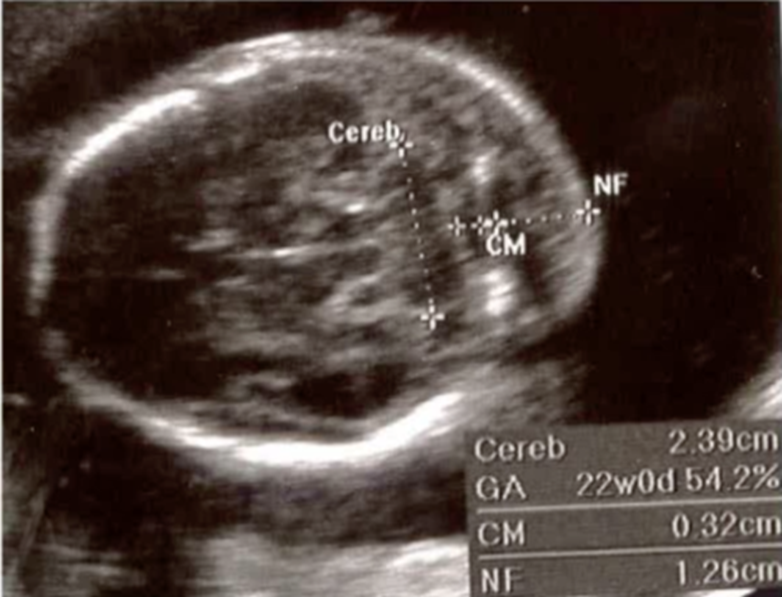

cerebellum and cisterna magna

when measuring nuchal fold what do you have to have in image

CSP

nuchal fold where to measure

outer skull to outer skin

thickened nuchal fold

cisterna magna should be less than

1cm

cerebellum has a ___:___ ratio in mm to gestational age from ___-___ weeks

1:1 ratio

16-24 weeks

nuchal fold measurement routinely performed ___ - ___ weeks

15-19.6

nuchal fold measurement should be less than ___ mm

6 mm

nuchal fold calipers